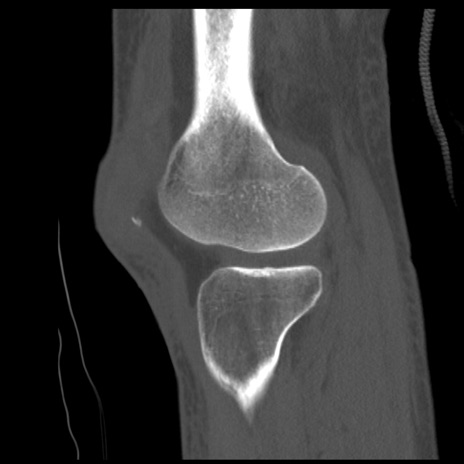

症例28 右膝関節CT(矢状断像)

右膝関節CT

冠状断像